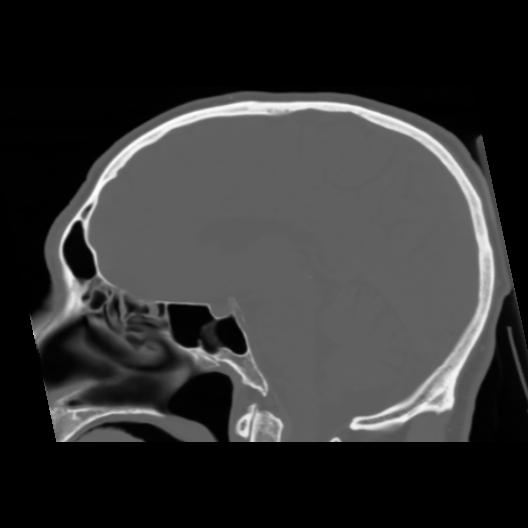

6 CEREBRO,,Sagittal,3.000,CEREBRO,Sagittal,